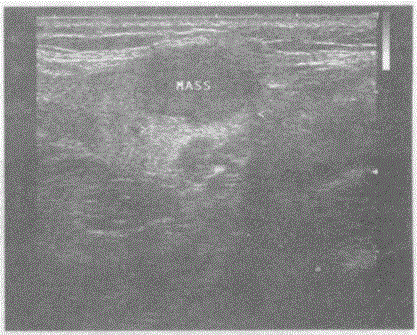

问题 临床资料:女,28岁,右颌下肿、不适两月余。 超声综合描述:右侧颌下腺可见1.5cm×1.1cm长圆形低回声,边界清晰,形态规则,内回声不均,后方声加强,CDFI:其内及周边可见血流信号。见下图及彩图82。 {图1} {图2} {图3} 超声提示:

选项 A.右腮腺囊性占位 B.右颌下腺实性占位 C.右腮腺混合性占位 D.右颈部肿大淋巴结

答案 B